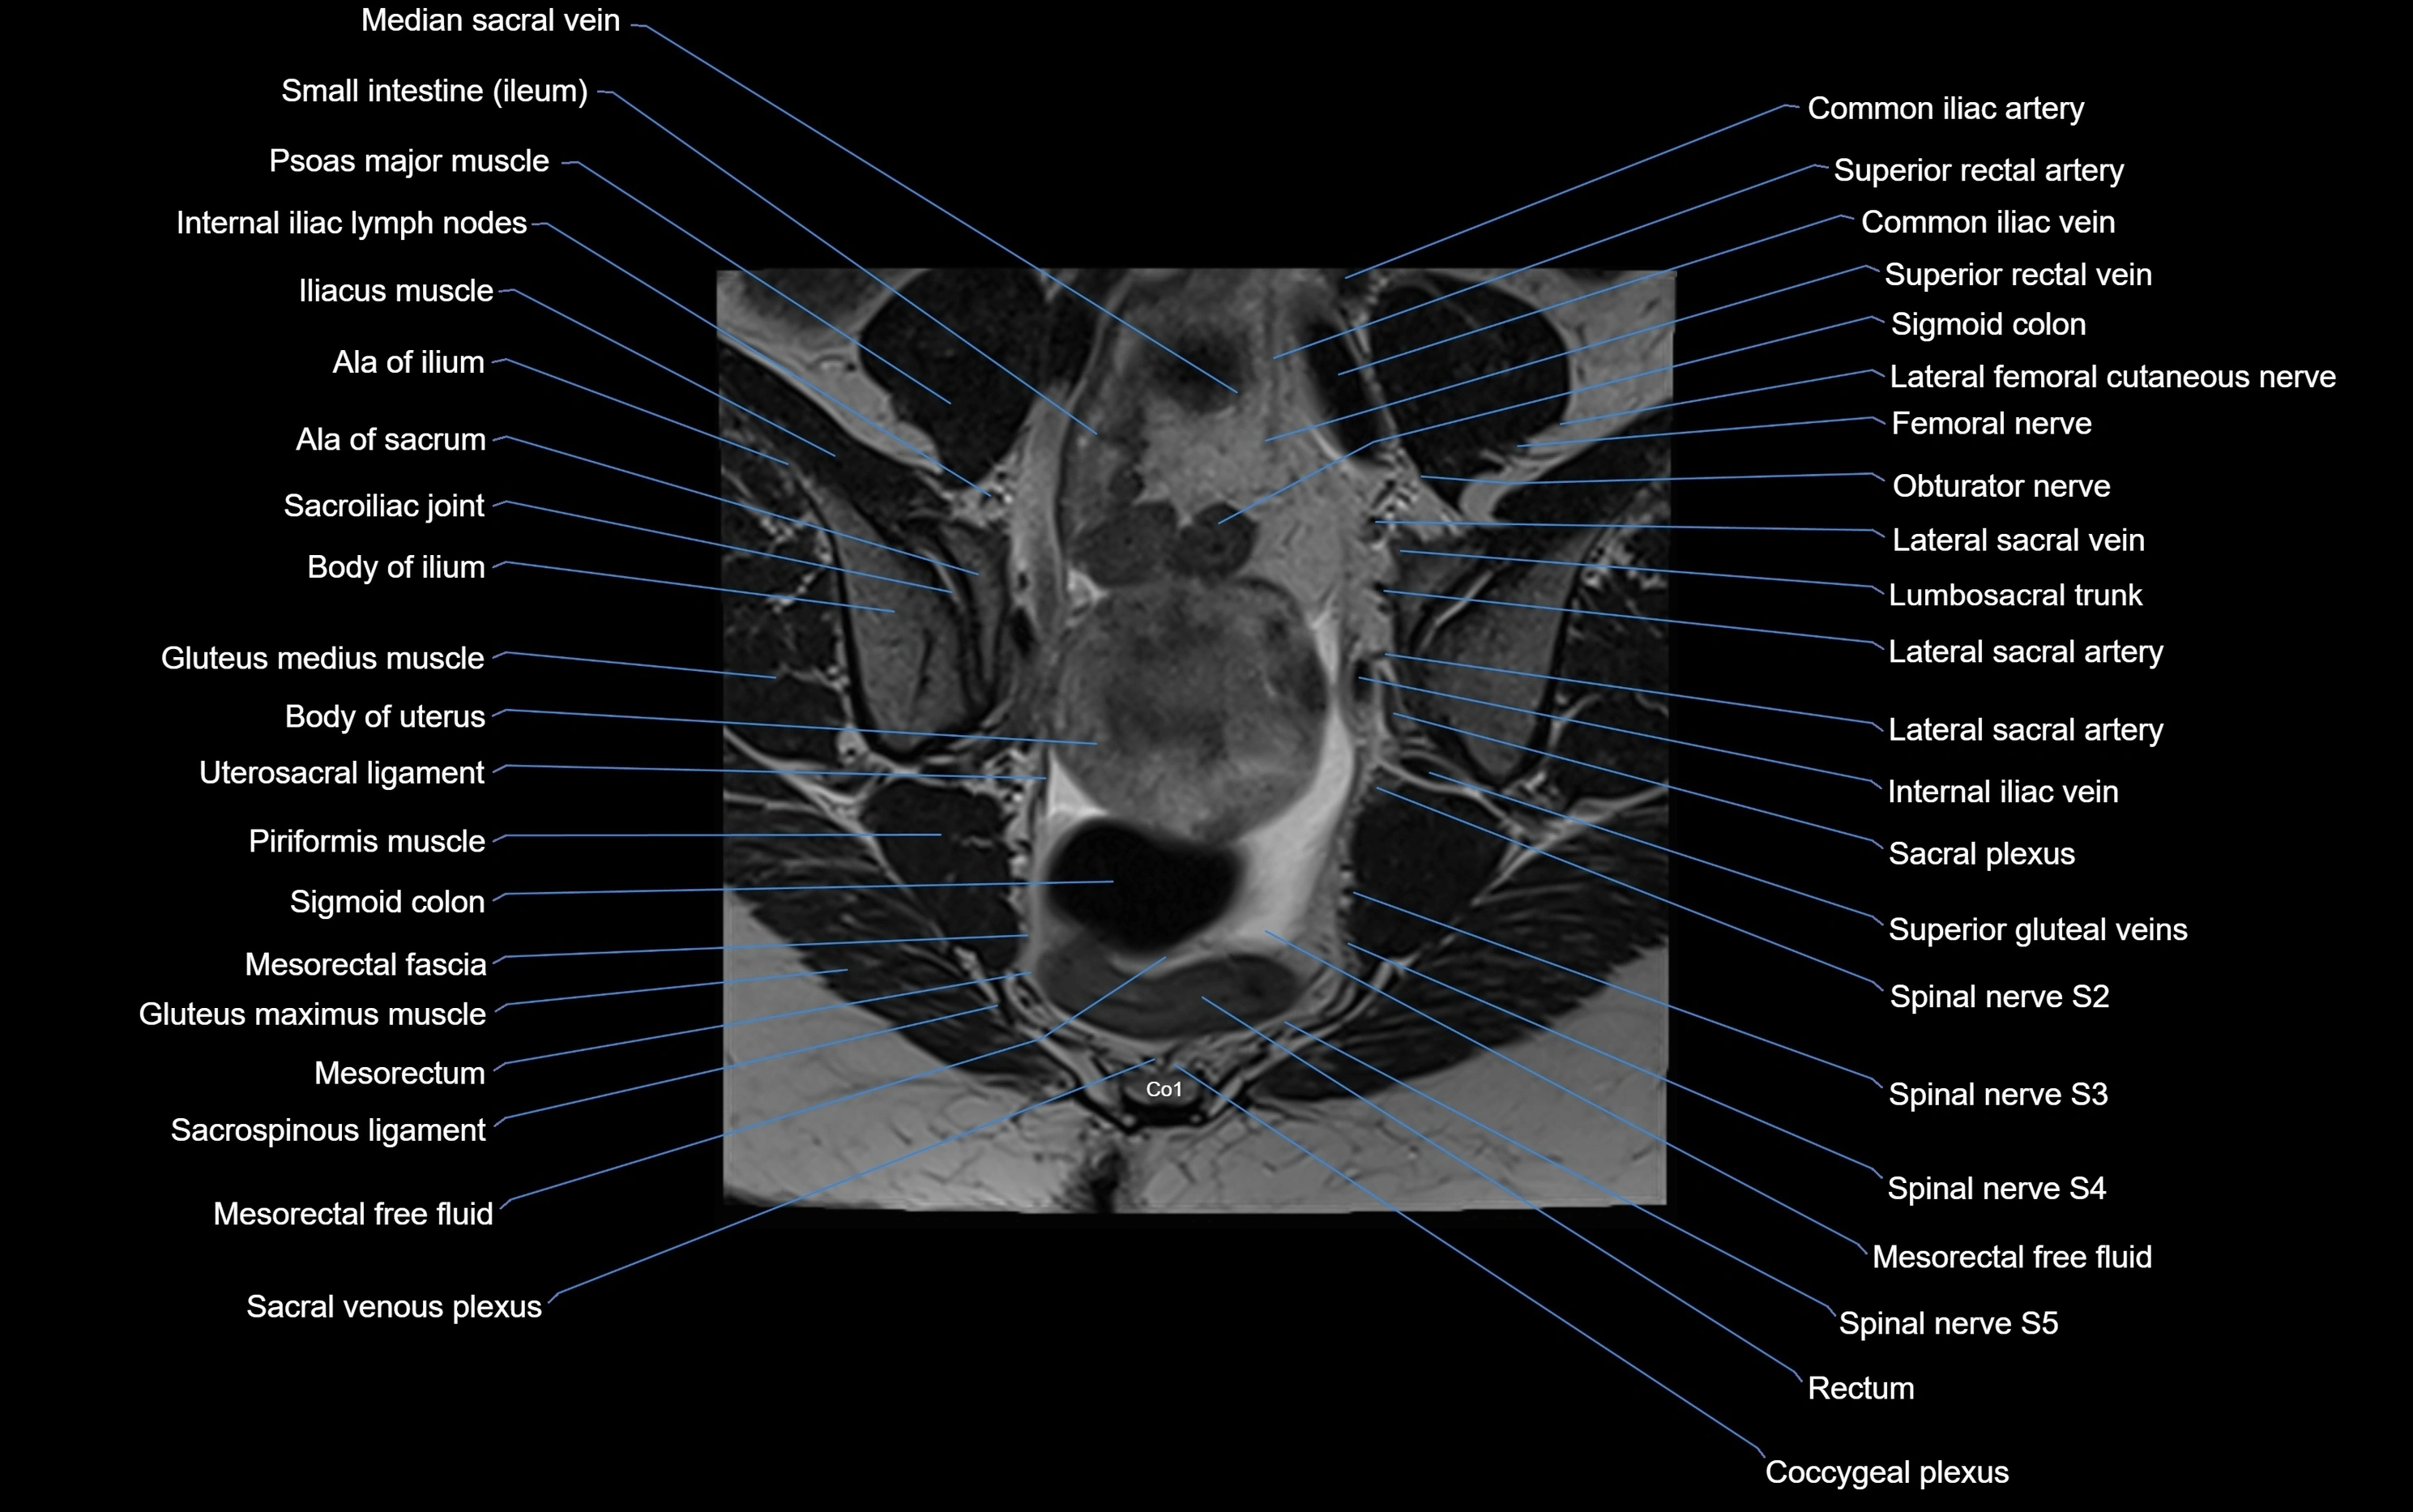

MRI image

image